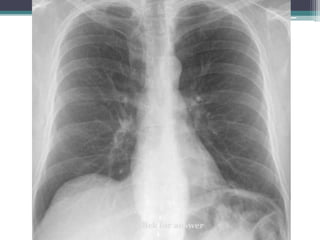

Which compartment do you think this mass is in?

Click for answer

Mass

โ€œdisappearsโ€

at clavicle

โ€ข Answer: Mass lies in anterior mediastinum. We

know this because it disappears at the level of the

clavicle where it extends into the neck.

โ€ข This particular example is Non-Hodgkins lymphoma